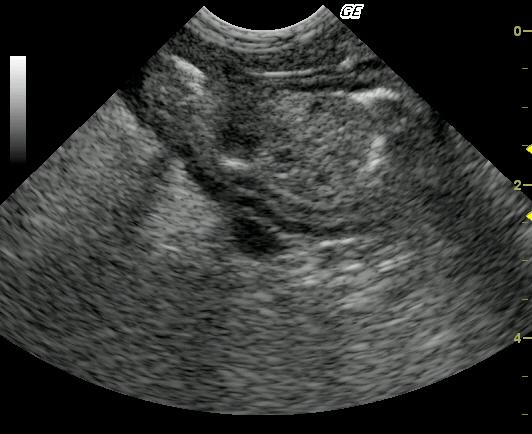

This 10 year old neutered male Beagle cross was presented for altered behavior. The physical exam was normal. CBC was normal while the blood chemistry revealed moderately elevated SAP and a slightly elevated total protein and slightly elevated globulin. The urinalysis revealed USG of 1.021 and 4+ proteinuria with inactive sediment. ACTH stimulation test was normal.